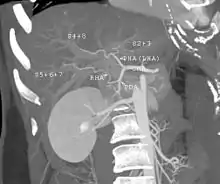

The large majority of liver transplants use the entire liver from a non-living donor for the transplant, particularly for adult recipients. A major advance in pediatric liver transplantation was the development of reduced size liver transplantation, in which a portion of an adult liver is used for an infant or small child. Further developments in this area included split liver transplantation, in which one liver is used for transplants for two recipients, and living donor liver transplantation, in which a portion of a healthy person's liver is removed and used as the allograft. Living donor liver transplantation for pediatric recipients involves removal of approximately 20% of the liver (Couinaud segments 2 and 3).

In a typical adult recipient LDLT, 55 to 70% of the liver (the right lobe) is removed from a healthy living donor. The donor's liver will regenerate approaching 100% function within 4–6 weeks, and will almost reach full volumetric size with recapitulation of the normal structure soon thereafter. It may be possible to remove up to 70% of the liver from a healthy living donor without harm in most cases. The transplanted portion will reach full function and the appropriate size in the recipient as well, although it will take longer than for the donor.[14]